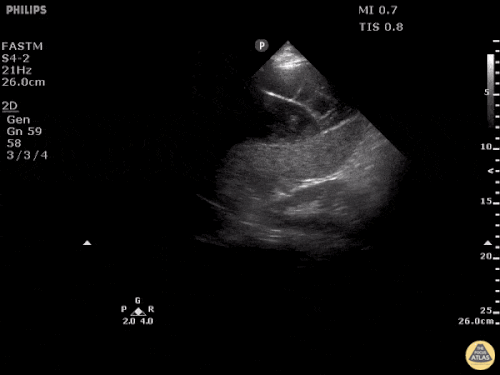

Sağ ventrikül fonksiyonunun değerlendirilmesi

Sağ ventrikül, önceki bölümde anlatılan temel kardiyak pencereler kullanılarak değerlendirilebilir. Normalde sağ ventrikül düşük basınçlı bir odacıktır ve sol ventriküle kıyasla daha küçük görünür.

Apikal dört boşluk görüntüsünde sağ ventrikül normalde sol ventrikülün yaklaşık üçte ikisi büyüklüğünde olmalıdır. Eğer iki ventrikül aynı boyutta görünüyorsa bu durum anormal kabul edilir ve dilatasyon düşündürür.

Kalp: Sağ Ventrikül Disfonksiyonu Örnekleri

PSSA’da RV Dilatasyonu ve D-Bulgusu ile Sağ Ventrikül Straini

Sağ Ventrikül Yetmezliği